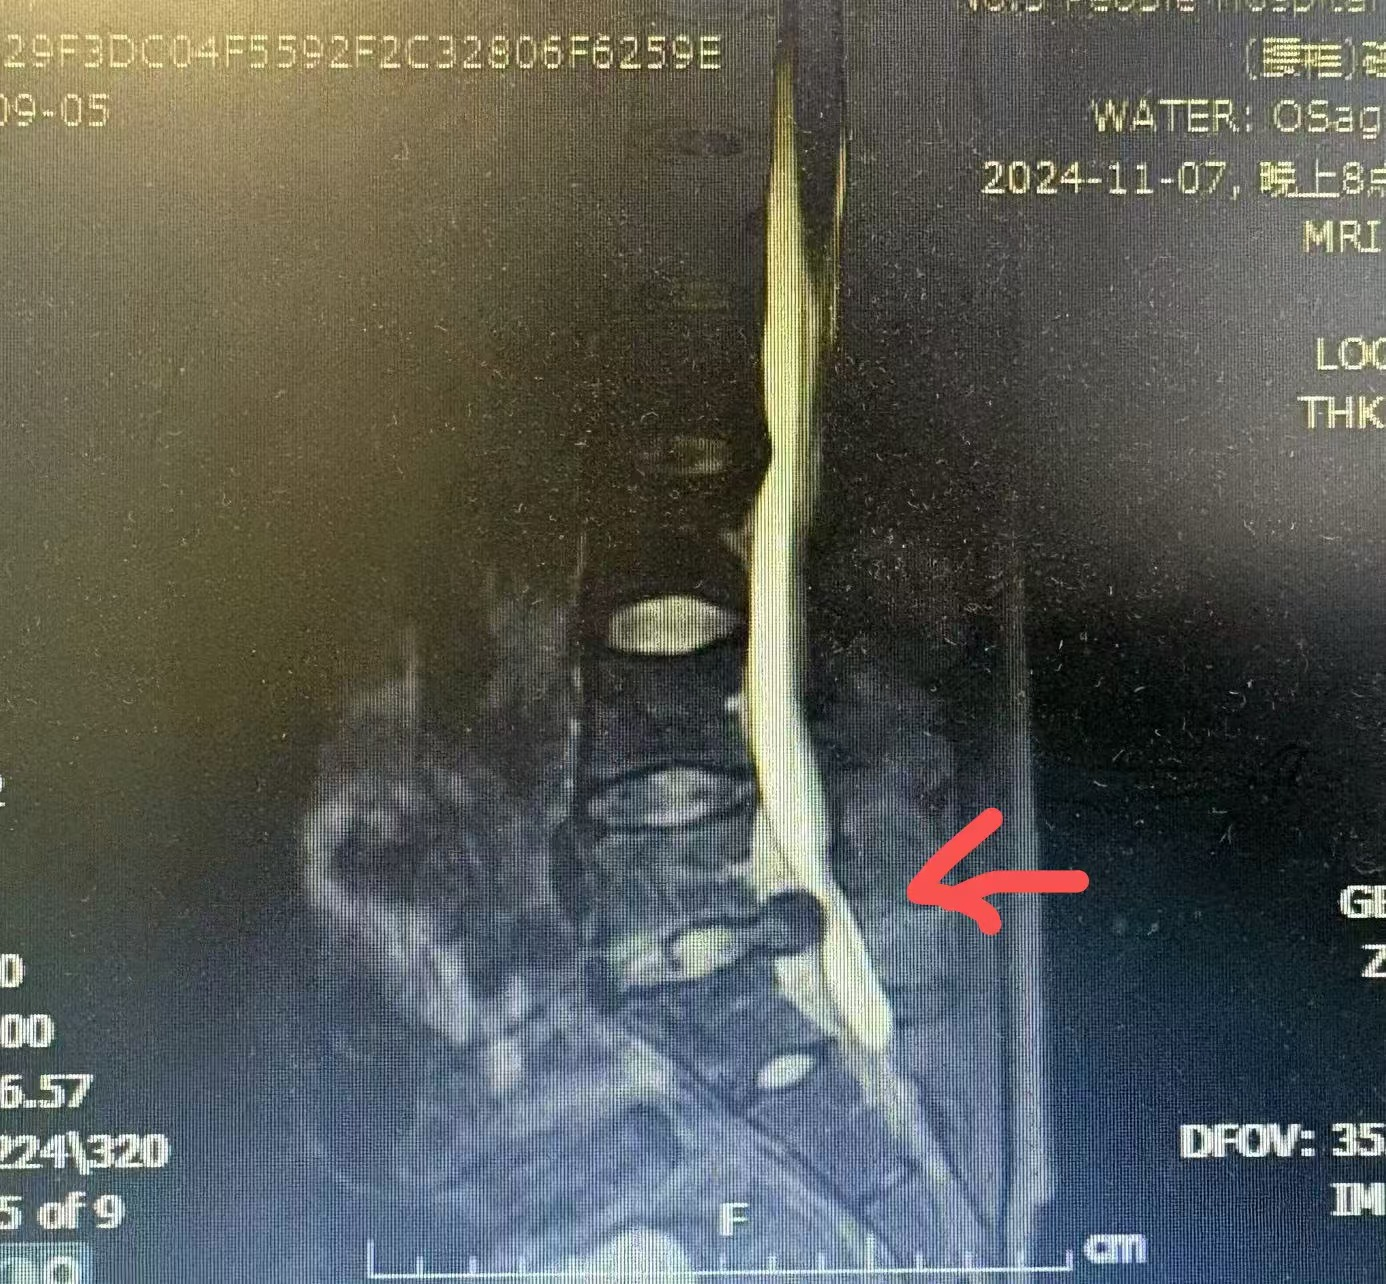

核磁共振可见明显大块髓核脱出